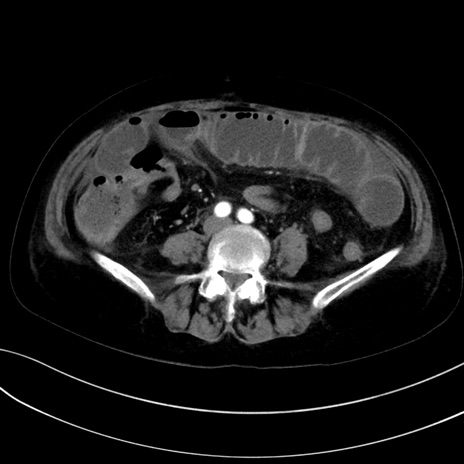

症例13 CT(横断像)1日半後